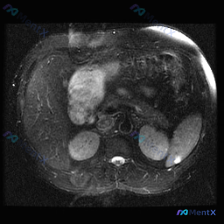

今天看到一份腹部MRI的T2WI图像,焦点在脾脏,整理一下读片的思考过程,避免踩坑。 先看核心影像表现 这是一张轴位T2WI,最突出的异常在脾脏: - 信号:脾实质内有数个类圆形极高信号影,信号强度接近脑脊液,提示是液体(浆液性为主)。 - 形态:边界清晰,但边缘呈分叶状,囊腔之间相互融合或紧邻,不...

最近看到一张腹部MRI的T2加权轴位片,最初的焦点是“脾脏病变”,但仔细梳理下来,觉得这个病例的阅片思路特别有借鉴意义,整理出来和大家分享。 先看病例的影像客观发现 - 肝脏:右叶可见一处类圆形高信号影,边界清晰锐利,信号均匀; - 脾脏:外后缘可见一处类圆形高信号影,边界清晰,信号均匀; - 左肾...